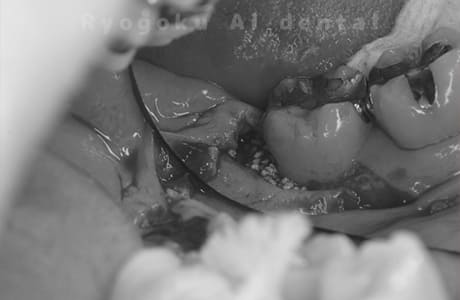

STEP 4

- 再生療法

- 歯周ポケットの深いところを歯ぐきを開いて外科的にアプローチを行います。